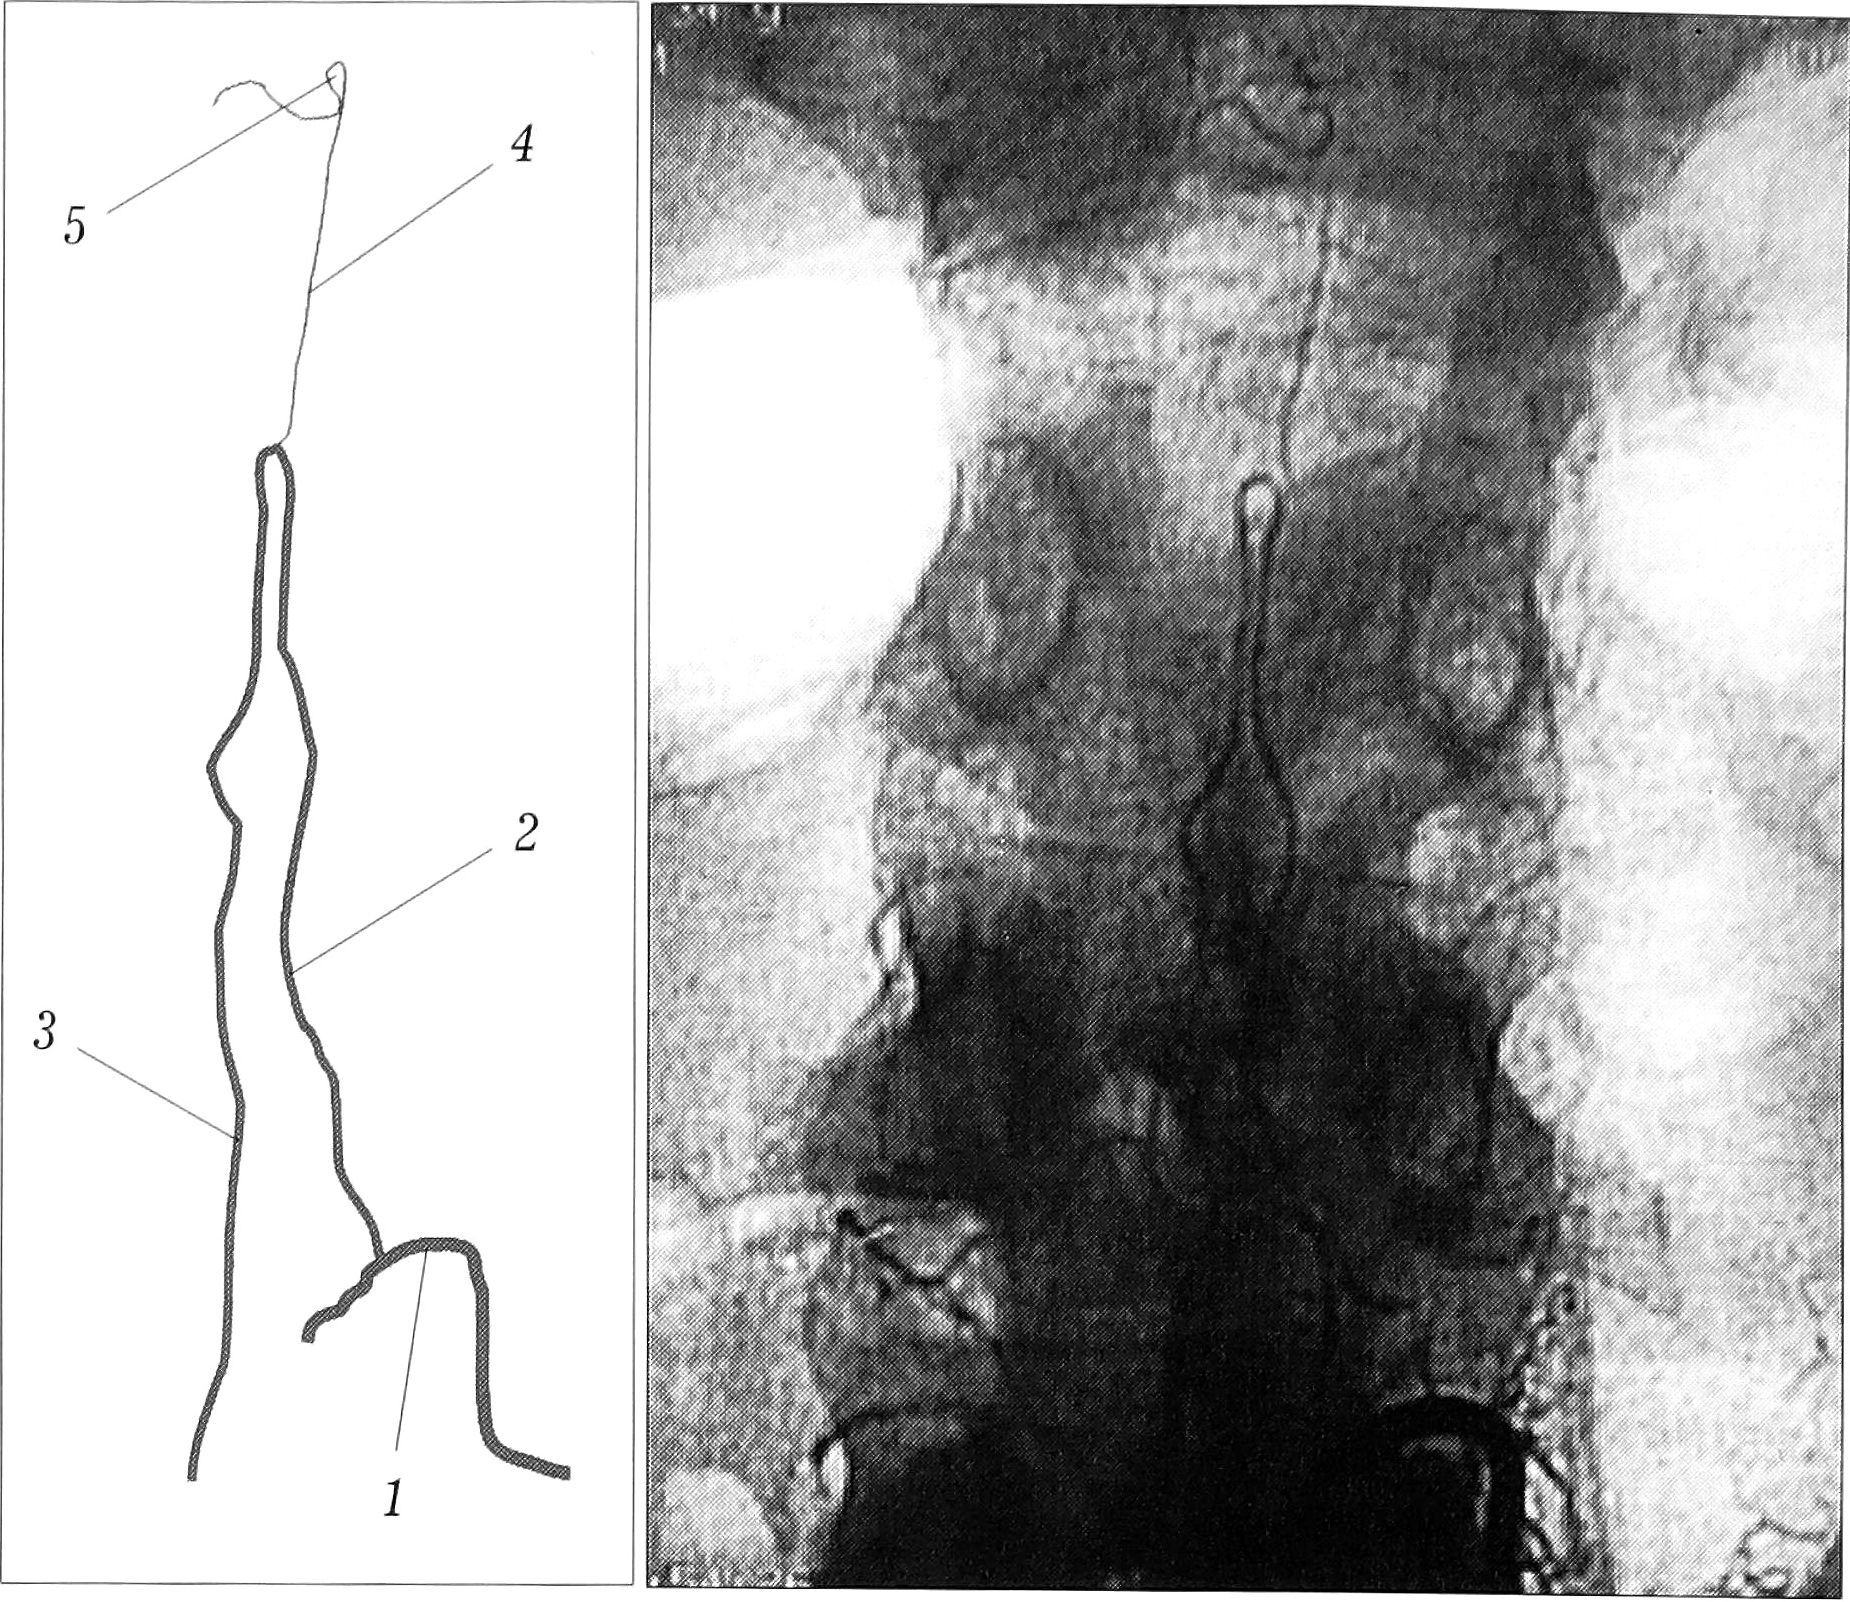

У всех пациентов выполняли спинальную ангиографию, ангиографию межреберных артерий, у больных с локализацией травмы в шейном или верхнегрудном отделе позвоночника — ангиографию затылочных артерий. Особое внимание уделяли исследованию кровоснабжения в области травмы спинного мозга. Для этого применяли спинальную ангиографию по методике Т.П. Тиссена [6]. При травме шейного отдела спинного мозга производили селективную катетеризацию с контрастированием спинальных артерий. Контрастное вещество вводили вручную до появления изображения передних радикуломедуллярных артерий. Исследование заканчивали после получения полного изображения передней спинальной артерии в зоне травмы и выше- и нижележащих отделов спинного мозга (рис.З).

Рис. 3. Спинальная ангиограмма больного Л. 29 лет. Окклюзия передней спинальной артерии. 1 — поясничнаая артерия L1; 2 — артерия Адамкевича; 3 — нисходящий отдел передней спинальной артерии; 4 — восходящий отдел передней спинальной артерии; 5 — окклюзия передней спинальной артерии.

При анализе ангиограмм определяли локализацию артерии Адамкевича, уровень ее отхождения от соответствующей межреберной или поясничной артерии, сторону отхождения, а также кровоснабжаемый ею бассейн передней спинальной артерии.